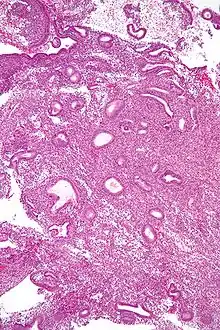

Biopsie endométriale révélant une hyperplasie simple.

L'hyperplasie endométriale est une prolifération bénigne de l'endomètre dans l'utérus. L'hyperplasie endométriale est classée en fonction de sa cytologie et du tissu glandulaire. Elle peut être simple, complexe et atypique, avec un risque croissant d'évolution vers un cancer de l'endomètre.